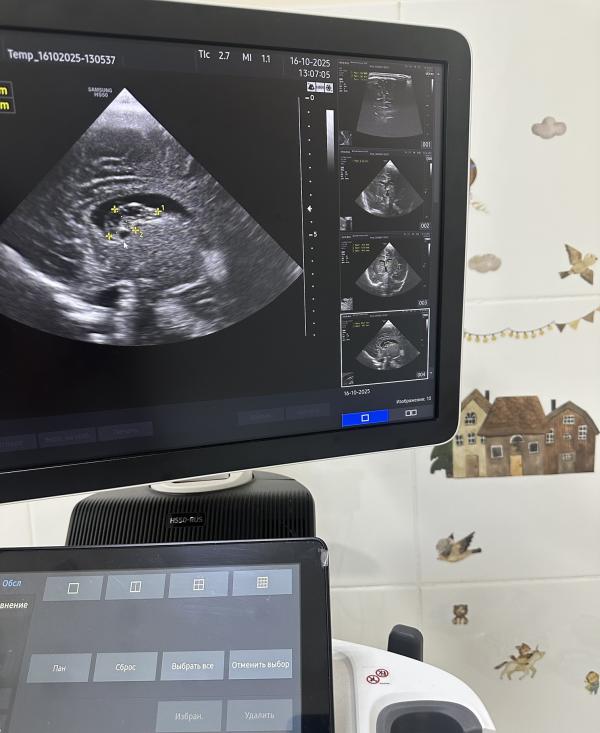

На УЗИ вчера был абсолютно здоровый доношенный малыш, роды естественные, в срок. Единственным моментом стало то, что нейросонография проводилась в возрасте двух месяцев, и мама слегка расстроилась, узнав о наличии кист и небольшом расширении боковых желудочков.

*на узи-снимках указаны кисты и их измерения